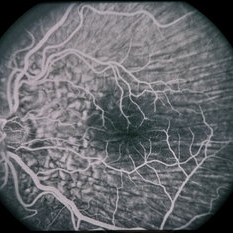

45-year-old Hispanic male with hypotony from over-filtration.